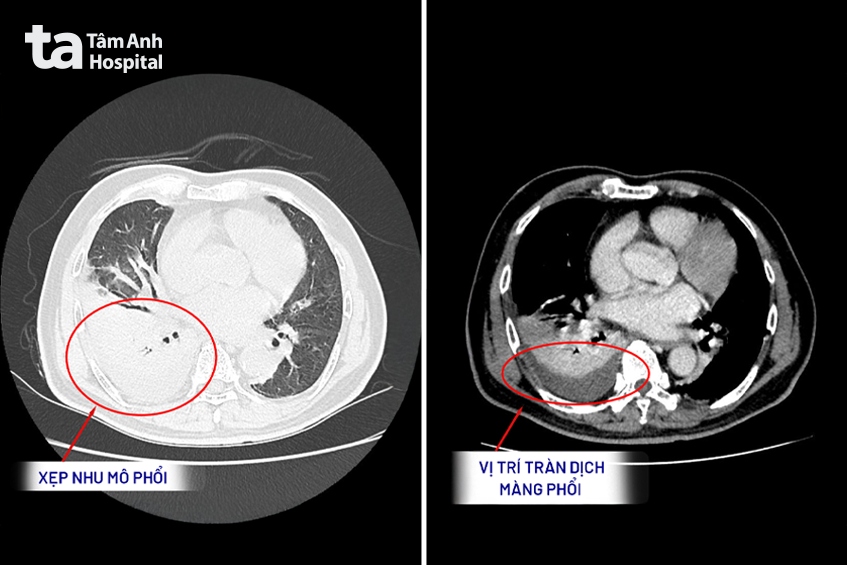

Tại Bệnh viện Đa khoa Tâm Anh TP.HCM (cơ sở P.Tân Hưng – Q.7 cũ), TS.BS Trần Minh Giang, đơn vị Nội Tổng quát chỉ định thực hiện chụp CT tầm soát phổi liều thấp. Kết quả cho thấy người bệnh bị tràn dịch hai bên màng phổi, tức là có một lượng lớn dịch bất thường bao quanh phổi, làm phổi không thể nở ra bình thường khi hít thở.

Người bệnh đã được chọc dẫn lưu dịch màng phổi để phổi có thêm không gian nở ra, từ đó cải thiện tình trạng khó thở, đồng thời sử dụng thuốc điều trị nhiễm trùng theo hướng viêm phổi nặng. Các xét nghiệm máu cho thấy chỉ số viêm tăng cao, phản ánh cơ thể đang có phản ứng viêm hoặc nhiễm trùng mạnh.

Sau 6 tuần điều trị phối hợp kháng sinh và kháng nấm, tình trạng của ông Tỉnh cải thiện hoàn toàn. Hình ảnh phổi trở lại thông khí tốt, không còn tình trạng tràn dịch “trắng xóa” như trước.